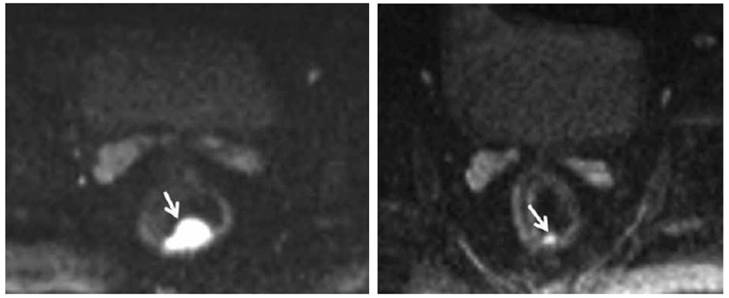

Lambregts et al. studied a total of 120 patients with locally advanced rectal cancer from three university hospitals who underwent chemoradiation therapy followed by standard T2 weighted-MRI and diffusion weighted imaging (DWI) (Figures 4 and 5). The sensitivity for selection of complete responders ranged from 0-40% on standard MRI versus 52-64% after the addition of DWI. They concluded that MRI+ DWI could significantly improve sensitivity for selection of complete responders.39 Furthermore, specificity is greater than 90%, which indicates that the risk for underestimation of residual tumor can be brought to <10%. As an adjunct to clinical tools (i.e., DRE, endoscopy, and biopsy), the combined use of MRI +DWI seems promising to enable a more precise selection of patients eligible to undergo less invasive treatments. The current results are obviously still premature for clinical decision-making, but its promise warrants further large and prospective patient studies.

Figure 4

Pre-chemoradiation therapy (CRT) DW-MRI (left) shows a 4.8 cc, polypoid rectal tumor with very high signal intensity (arrow). Post-CRT DW-MRI (right) shows a significant decrease in tumor volume (1 cc). Residual tumor with intermediate signal intensity limited to the mucosa and submucosa can be seen (arrow). Courtesy of Engin, et al. 63